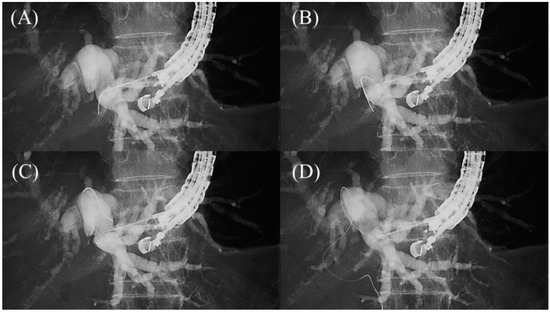

- Hamada, T.; Nakai, Y.; Isayama, H.; Koike, K. Tandem stent placement as a rescue for stent misplacement in endoscopic ultrasonography-guided hepaticogastrostomy. Dig. Endosc. 2013, 25, 340–341. [Google Scholar] [CrossRef]

- Miyano, A.; Ogura, T.; Yamamoto, K.; Okuda, A.; Nishioka, N.; Higuchi, K. Clinical Impact of the Intra-scope Channel Stent Release Technique in Preventing Stent Migration During EUS-Guided Hepaticogastrostomy. J. Gastrointest. Surg. 2018, 22, 1312–1318. [Google Scholar] [CrossRef]

- Uchida, D.; Kawamoto, H.; Kato, H.; Goto, D.; Tomoda, T.; Matsumoto, K.; Yamamoto, N.; Horiguchi, S.; Tsutsumi, K.; Okada, H. The intra-conduit release method is useful for avoiding migration of metallic stents during EUS-guided hepaticogastrostomy (with video). J. Med. Ultrason 2018, 45, 399–403. [Google Scholar] [CrossRef]